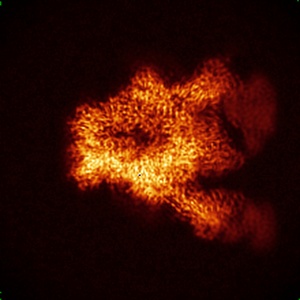

Cryo-EM structure of ConSOSL.UFO.664 (ConS) in complex with bNAb PGT122

Single-particle3.12 Å

Sample: ConSOSL.UFO.664 in complex with bNAb PGT122